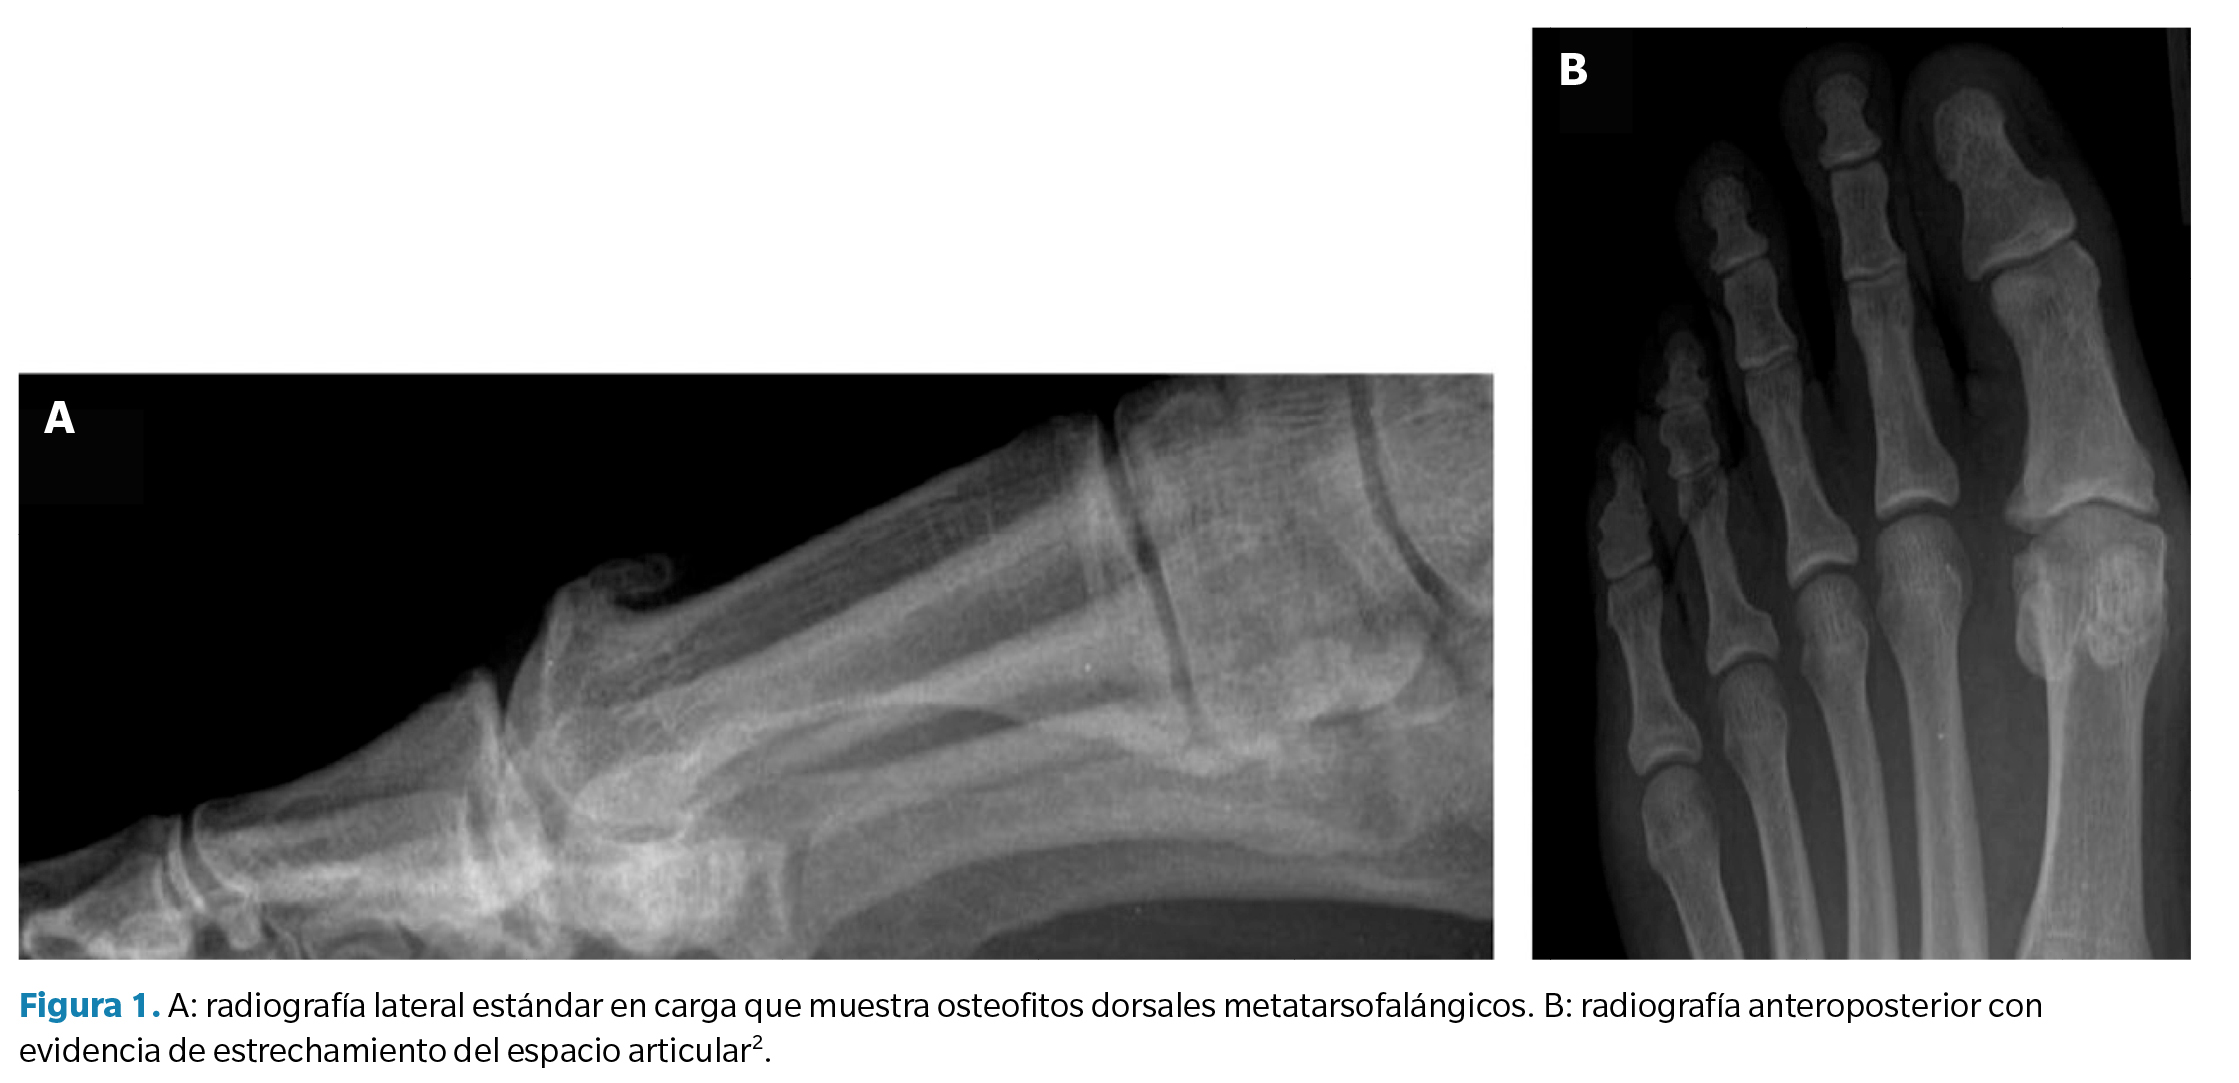

La evaluación radiológica del HR se basa en una radiografía en proyección anteroposterior y lateral en carga (Figura 1). Estas pruebas de imagen permiten la toma de decisiones quirúrgicas enfocándose hacia técnicas de conservación articular (queilectomía), osteotomías capitales, artroplastias o técnicas de fusión articular (artrodesis) en enfermedades más desarrolladas. Se recomienda la utilización de radiografías laterales para la identificación de osteofitos dorsales y para la valoración de la reducción del espacio articular de la primera AMT.